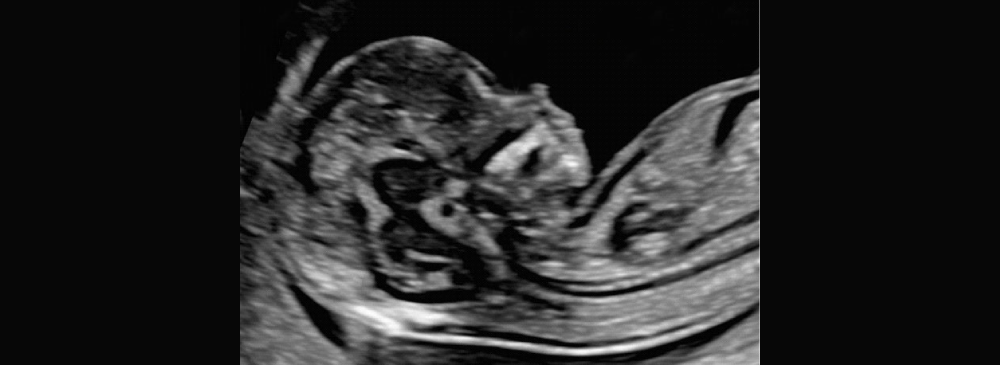

Understanding your baby’s development in the earliest stages of pregnancy is both exciting and critical. At our advanced NT Scan Centre in Pallavaram, we provide high-quality, accurate, and timely NT (Nuchal Translucency) scans to support your prenatal care journey. Our centre combines the latest ultrasound technology with experienced radiologists to ensure precise assessment and complete peace of mind.

The NT scan plays a crucial role in the first trimester, often performed between 11 and 14 weeks of gestation. It helps detect early signs of chromosomal abnormalities like Down syndrome, and also provides insights into your baby's growth and heartbeat. Choosing the right diagnostic centre for this scan ensures accurate results and a smooth experience for expecting mothers.

An NT scan, or Nuchal Translucency scan, is a specialized ultrasound that measures the fluid-filled space at the back of your baby’s neck. This scan is typically done between 11 and 14 weeks of pregnancy and forms an important part of the first trimester screening tests. The NT measurement, combined with your blood test and maternal age, helps assess the risk of chromosomal abnormalities such as Down syndrome (Trisomy 21), Edwards syndrome (Trisomy 18), and Patau syndrome (Trisomy 13).

The NT scan is completely safe and non-invasive for both the mother and baby. It offers critical insights into fetal development and identifies potential structural issues early in the pregnancy. Although it does not provide a diagnosis, it helps determine whether further testing, like NIPT or diagnostic procedures, may be needed.

During the NT scan, you’ll lie comfortably on the examination bed while the technician applies gel over your lower abdomen. A transducer (ultrasound probe) is then moved across the abdomen to capture images of the fetus. The radiologist will measure the clear (translucent) space at the back of the baby’s neck, which is the key part of the scan.

In some cases, if the baby’s position does not allow for a clear view, the technician may ask you to shift positions or walk around for a while before retrying. The entire scan typically takes about 20 to 30 minutes and results are usually available the same day or within 24 hours.